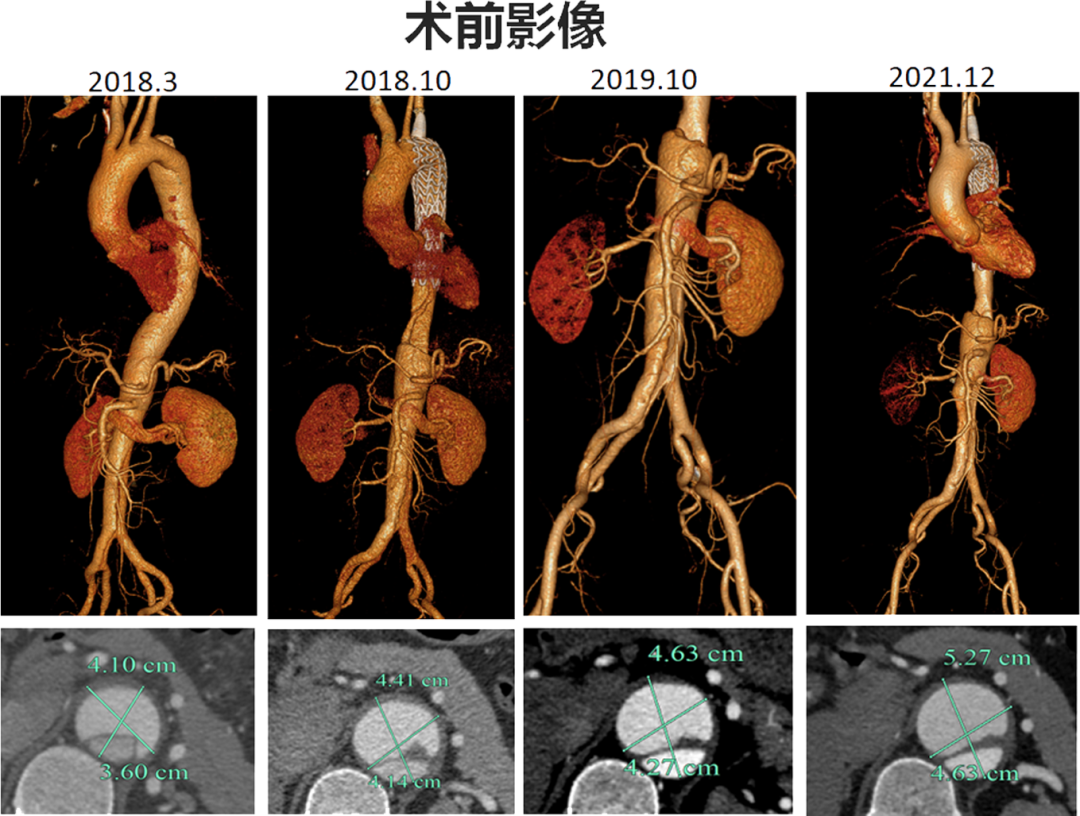

►►►随访影像:患者降主动脉夹层逐渐增大,以假腔增大为主,夹层动脉瘤直径为5.2cm

夹层近端封闭良好。夹层动脉瘤累及整个内脏区动脉,腹腔干、肠系膜上动脉假腔供血,腹腔干开口重度狭窄;右肾动脉真假腔供血,以假腔为主;左肾动脉真腔供血。肾下腹主动脉段无裂口,右侧髂外动脉存在裂口。

CT影像